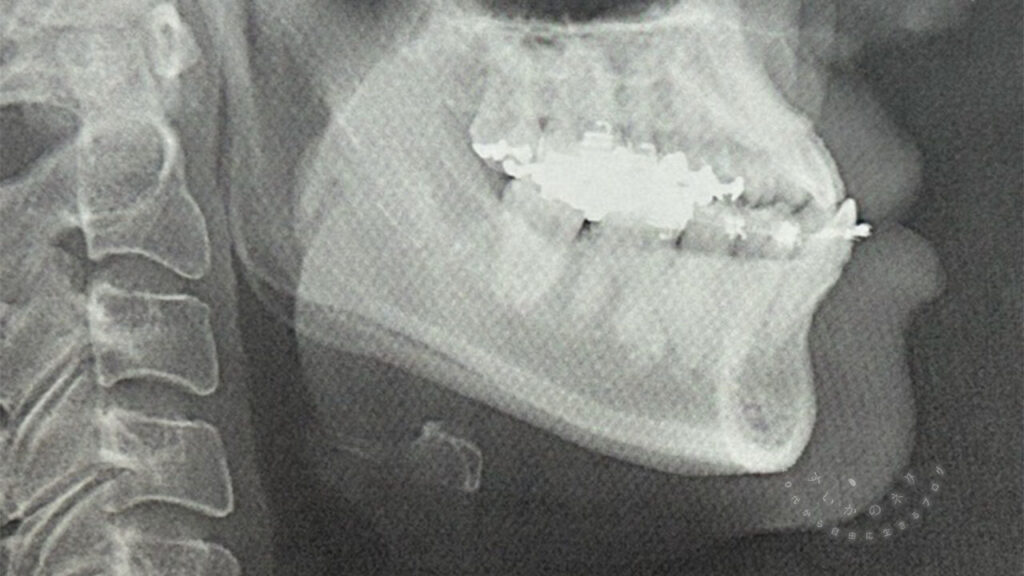

2025年10月現在、40代半ば、顎変形症の治療がはじまって1ヶ月くらいが経過したところです。

顎変形症ってどんな病気?

顎変形症は病気です。

どんな病気?かというと、

顎変形症(がくへんけいしょう)とは、上あご(上顎骨)または下あご(下顎骨)あるいはその両方の大きさや形、位置などの異常によって、顔面の変形と、かみ合わせの異常を起こしている状態をいう。

「顎変形症」(2025年2月4日 (火) 21:27 UTCの版)『ウィキペディア日本語版』。

これらは症状の一部ですが、簡単にいえば顎の異常のことだそうです。

この5つなら出っ歯以外すべてに該当していた私(白目)

幼少期から、下の歯が上の歯よりも前に出ているのはずっと気になっていました。